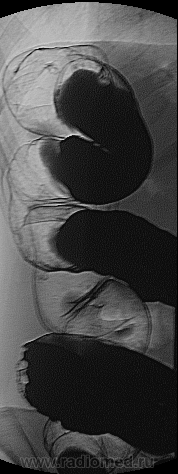

Женщина 53 года, после проведения колоноскопии направлена к нам:

"Аппарат проведен до селезеночного угла.Дальнейшее исследование прекращено из-за выраженного болевого синдрома.В с/3 сигмовидной кишки на 3/4 стенки , протяженностью до 3 см, видны аденоматозные разрастания. Щипковая биопсия №6.Стенки толстой кишки эластичные.Слизистая оболочка осмотренной кишки умеренно гиперемирована, истончена.Сосудистый рисунок выраженный. ЗАКЛЮЧЕНИЕ: Аденоматозные разрастания сигмовидной кишки"

К сожелению сделаны только прицельные снимки, но могу расписать на каких снимках какие отделы:

1й и 2й снимочки сделаны сигмовидный отдел ободочной кишки, частично ректо-сигмоидный;

3й снимок поперечный отдел ободочной кишки;

4й снимок прямая кишка;

5й снимок нисходящий отдел ободочной кишки;

6й снимок нисходящий отдел ободочной кишки;

7й снимок селезёночного угла ободочной кишки;

8й снимок печеночного угла ободочной кишки;

9й снимок прямой кишки;

10й снимок пытался вывести "сигму" без контраста;

Всё же я бы не сказал, что это свидетельствует в пользу б.Крона, 3ст. дисплазии это "пред рак", а если учесть что края подрыты и участок региден, правда местами имеет место быть бугристость рельефа от аденоматозного растрастания, мне кажется следует перебрать биоптат.